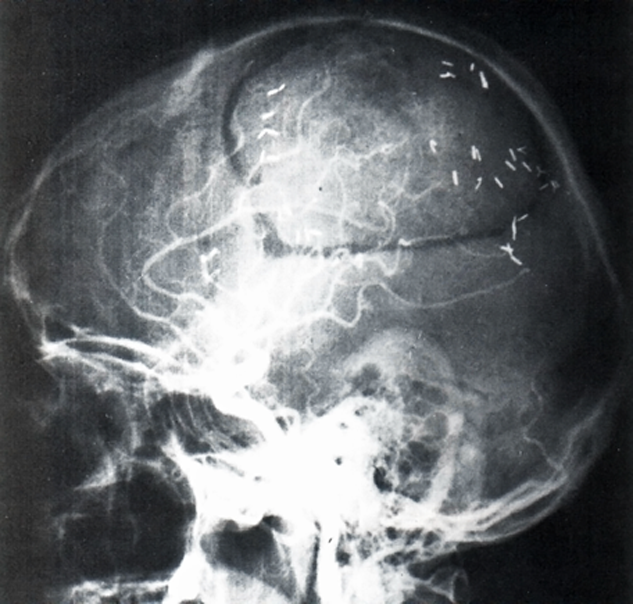

spaceholder redForeign bodies. Hemostatic or other clips in the CNS can move in their position (Figure 18-08). Dislocation by magnetic attraction or torque presents a risk of he­mor­rhage. In other parts of the body, we consider this to be a minimal risk, because af­ter the healing phase of six to eight weeks, fibrosis and encasement of the clip help to keep it in a stable position.

Figure 18-08:

X-ray of a head showing clips after a brain operation: safe or unsafe for MR imaging?